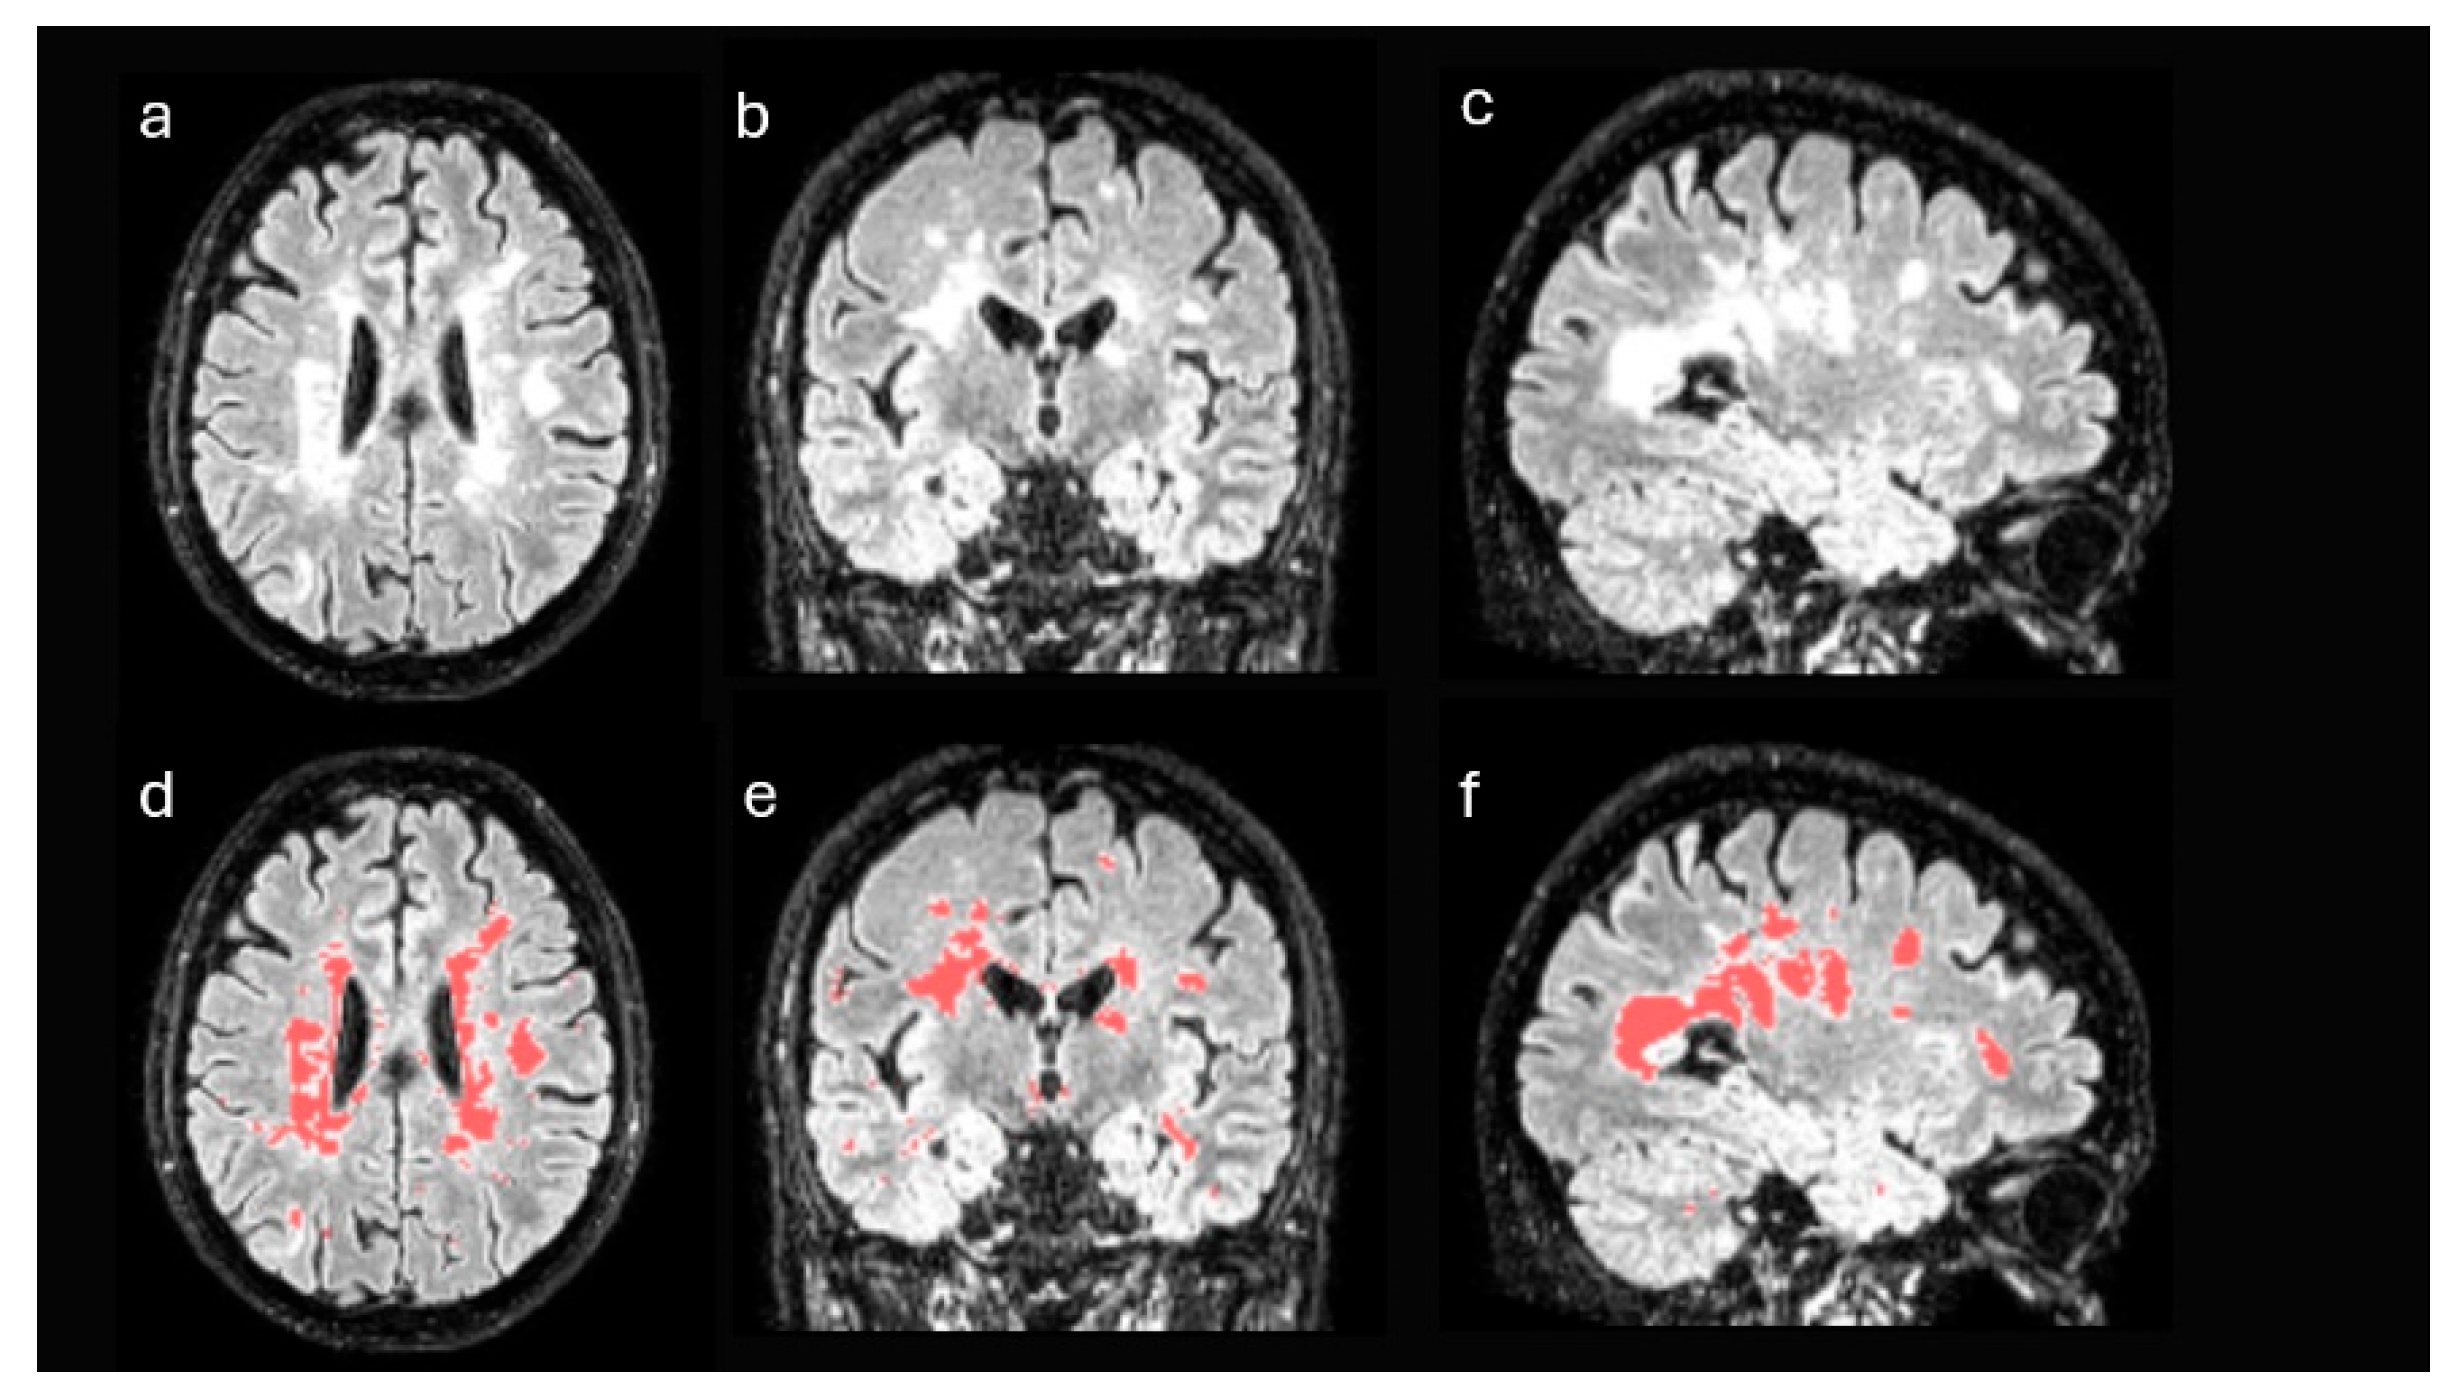

Figure 2. DWM segmentation of FLAIR MRI images. Axial (a), coronal (b), and sagittal (c) slices of the FLAIR MRI sequence. Following a semi-supervised thresholding procedure, a lesion mask was generated for each patient. Images (d), (e), and (f) show the segmentation (in red) of the damage white matter.

First, structural MRI FLAIR images of each patient were processed in order to identify disease-specific lesions. These images were registered to the standard Montreal Neurological Institute (MNI) space and segmented using the unified segmentation algorithm implemented in Statistical Parametric Mapping (SPM), version 12 [21]. After the process, the gray matter and white matter of each patient were selected in MNI space, discarding the remaining tissues. From these data and using a semi-supervised thresholding procedure, a mask with the lesions of each patient was generated (Figure 2). Using these masks, the lesion volume of each patient was obtained, both globally in the whole brain and in isolation in the WM. Likewise, the masks were used to estimate the volume of the non-damaged white matter of each patient, that is, the white matter excluding the areas affected by the disease.